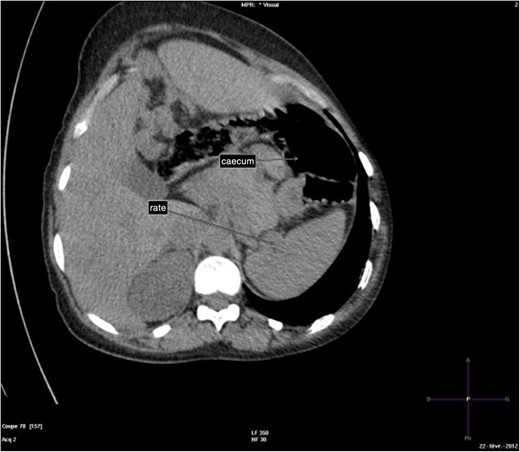

The abdominal-pelvic CT-scan showed a pre-splenic left position of the caecum and right colon, with no part of the colon on the right. The radiologist concluded that the patient was suffering from a complication of intestinal malrotation (IM) (Figs 1, 2, 3).

Abdominal-pelvic CT-scan, non-contrast enhanced, in the sagittal plane.